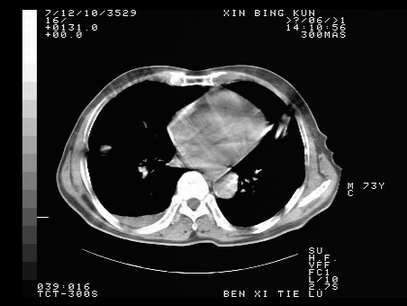

标题: CT10820:男,73岁,病史肺TB,现病史肺炎,直肠CA术后 [打印本页]

标题: CT10820:男,73岁,病史肺TB,现病史肺炎,直肠CA术后

双肺间质改变,依据病史双肺多发结节灶考虑转移,少量胸水.

1.两肺结核.2.两肺多发转移瘤.3右侧少量胸腔积液4.主动脉钙化.

双肺多发结节及条片状致密影,右侧少量胸腔积液。临床:直肠ca术后,肺tb病史。综合考虑:1 双肺转移!2 继发性肺结核合并感染!

此人病史较复杂,原有肺结核,直肠癌术后。肺部病灶形态亦呈多形性。因此,不可仅以一种病来解释肺部的病变。双肺多发的类圆形结节灶,结合病史还是首先考虑转移瘤,而双肺其余病灶还需结合化验室检查,结核或肺部感染在无其它检查资料的情况下不好排除。还是那句话----放射科医生不是开照像馆的,我们也是医生,看片一定要多结合临床及其它检查资料。要当一名合格的放射科医生,并不比当一名临床医生容易,我们可别把自已不当医生看。

两肺多发结节影,并见滋养动脉与其相连,考虑 两肺转移. 右侧胸腔积液考虑胸膜转移.

左肺上叶下叶背段,右肺中下叶见多发斑片状、条索状高密度影,兵变周围小结节影形成“树芽”样改变。 左肺上叶舌段近前胸壁处及右肺中叶内侧段见结节影。右侧胸膜腔内见液体密度区。纵隔内未见明确增大淋巴结。考虑左肺上叶舌段近前胸壁处及右肺中叶转移瘤可能性大。两肺继发型肺结核。右侧胸腔积液。